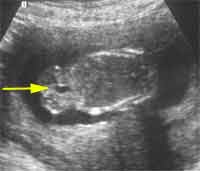

14 semaines